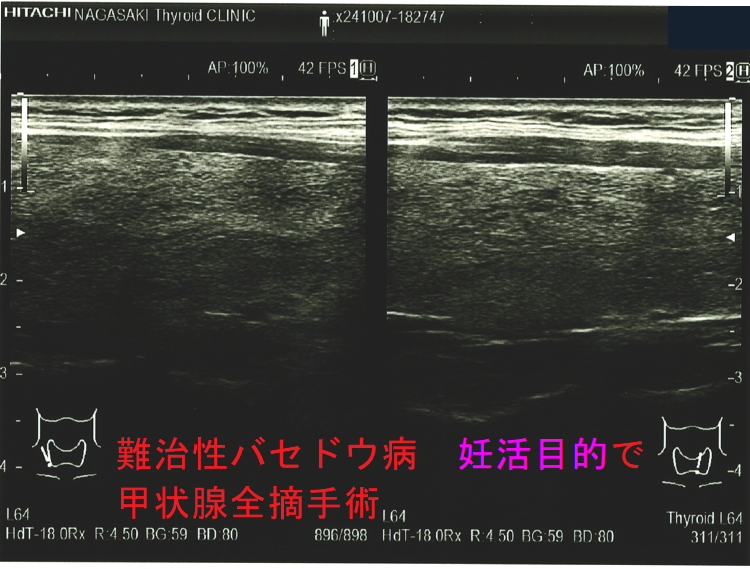

妊娠中、抗甲状腺薬(メルカゾール、プロパジール、チウラジール)+ヨウ化カリウム(KI)でもバセドウ病/甲状腺機能亢進症をコントロールできない時は、もはや妊娠2期(中期)の甲状腺全摘手術になります。[GUIDANCE TO THE MATERNAL, FETAL AND NEONATAL MANAGEMENT OF RESISTANCE GRAVE'S DISEASE IN PREGNANCY. Acta Endocrinol (Buchar). 2021 Oct-Dec;17(4):517-520.]

甲状腺全摘手術すれば母体の甲状腺機能は安定しますが、

- TSHレセプター抗体(TRAb)は急に下がらないため、妊娠20週以降に胎児の甲状腺を刺激して胎児バセドウ病、出生後の新生児バセドウ病は免れません。

- 妊娠3期(後期)の手術だと、母体の甲状腺ホルモンが胎児の脳下垂体にTSH(甲状腺刺激ホルモン)分泌抑制を掛けたままの出生になり、新生児一過性中枢性甲状腺機能低下症をおこす可能性があります。

妊娠中、抗甲状腺薬(メルカゾール、プロパジール、チウラジール)が副作用で使用できなくなった時は、妊娠2期(中期)に甲状腺全摘手術になります。妊娠1期(前期)に使用できなくなった時は、2期(中期)までヨウ化カリウム(KI)で持たせます。妊娠3期(後期)に使用できなくなった時は、出産後までヨウ化カリウム(KI)で持たせます。(第54回 日本甲状腺学会 P199 抗甲状腺薬の副作用のため手術療法を行い出産に至ったバセドウ病合併妊娠の一例)[Obstet Gynecol. 2013 Aug;122(2 Pt 2):490-492.][Korean J Intern Med. 2005 Dec;20(4):335-8.]

但し、バセドウ病抗体(TRAb,TSAb)が最も低下するのは、甲状腺全摘手術である事に変わりありません(妊娠希望バセドウ病女性の新たな選択肢:手術療法)。

最もバセドウ病抗体が低下するのが甲状腺全摘出手術です(Clin Endocrinol (Oxf). 2019 Feb;90(2):369-374.)。

以上より、長崎甲状腺クリニック(大阪)では、バセドウ病抗体が最も下がる甲状腺全摘出手術の方を勧めています。